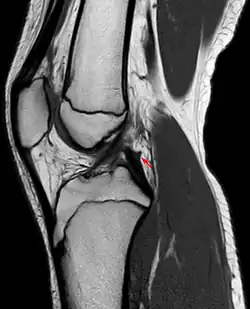

Posterior meniscofemoral ligament on MRI, coronal -

Posterior meniscofemoral ligament (Wrisberg) behind the posterior horn of the lateral meniscus close to its insertion. Sometimes wrongly interpreted as a meniscal tear.